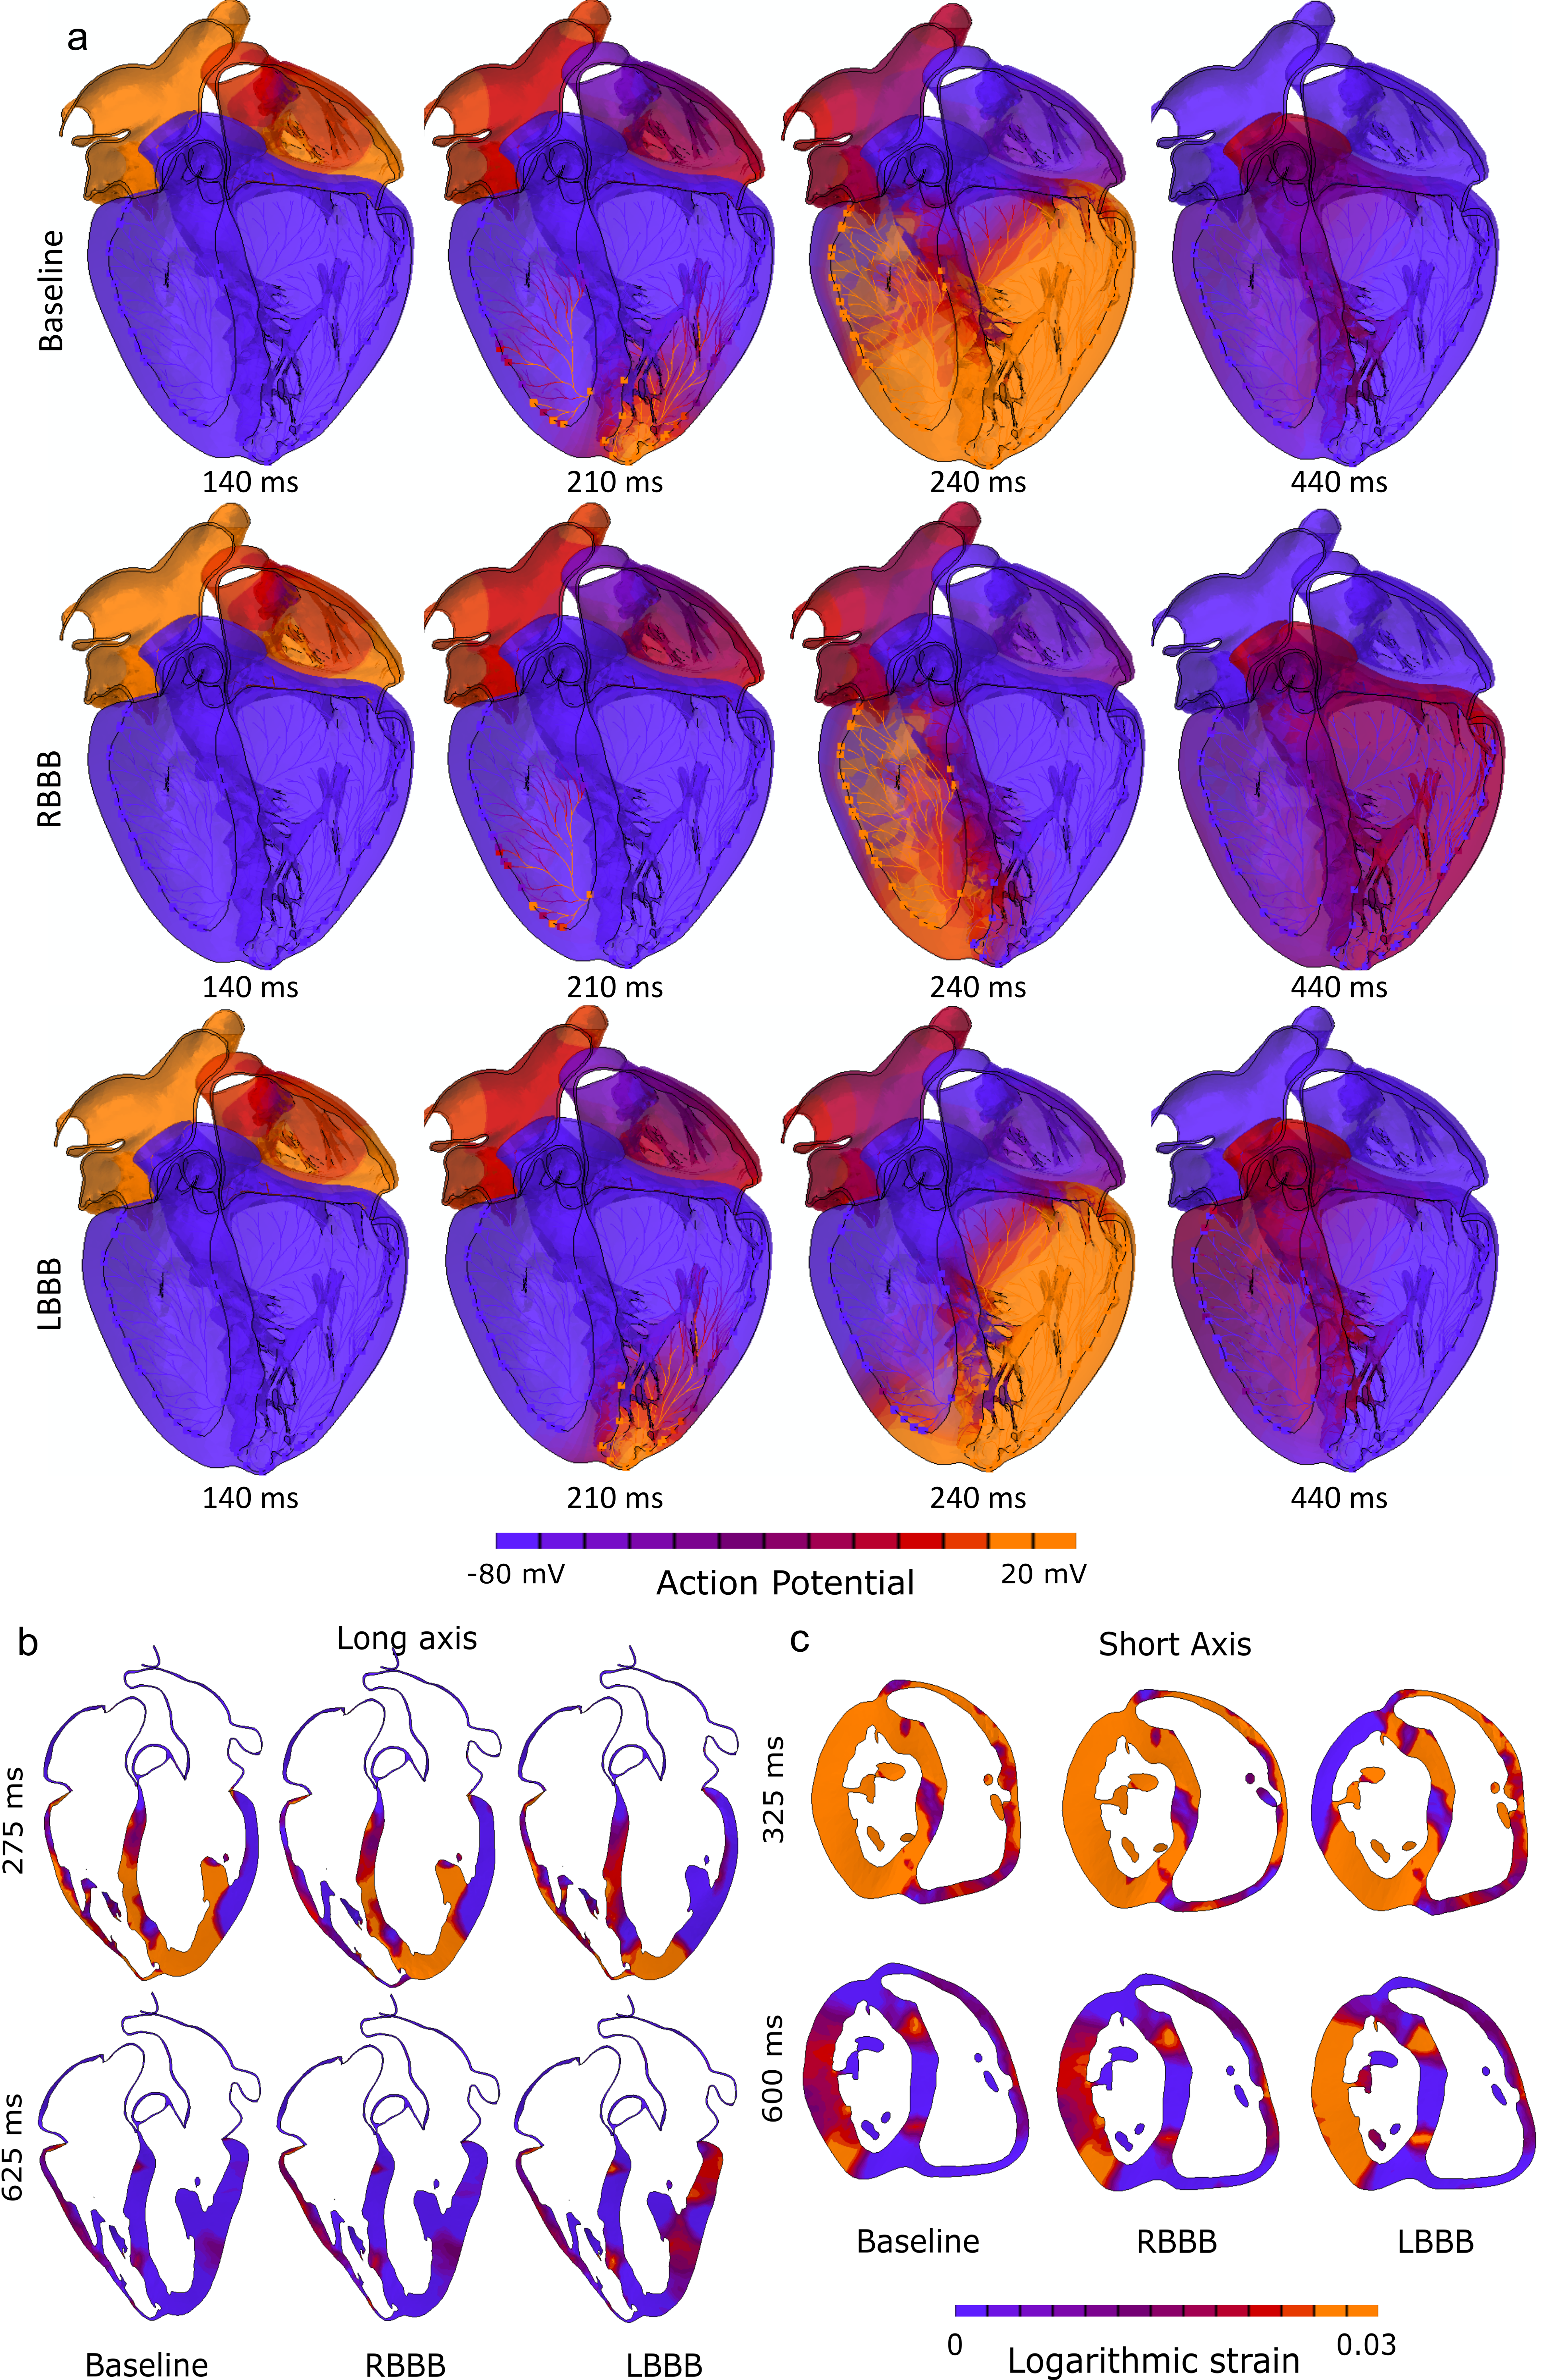

Risk Assessment of Post-TAVR Cardiac Conduction Abnormalities Asing A 'Digital Twin' of Human Heart

- Post-TAVR Cardiac conduction abnormalities (CCAs) occur due to mechanical damage sustained by the atrioventricular conduction system located near the inter-leaflet triangle region between the non-coronary and the right-coronary leaflet. In his study, we have used an electro-mechanically coupled beating heart model to develop an in-silico technique to assess CCA risk incorporating the effect of a dynamic beating heart and pre-procedural parameters such as implantation depth and preexisting cardiac asynchrony in the development of post-TAVR CCA.

TAVR Deployment in Living Human Heart Model (Electro-mechanically coupled)

Preexisting conduction abnormalities modeling

- Contact pressure, Contact Pressure Index (CPI), and stress components on the area of interest (AOI) were analyzed for three implantation depths and three preexisting conduction abnormalities scenarios.

- Lower implantation, and preexisting-right bundle branch block (RBBB) poses higher risk of post-TAVR CCA which is aligned with the clinical findings.

Publication link- Assessing Post-TAVR Cardiac Conduction Abnormalities Risk Using a Digital Twin of a Beating Heart